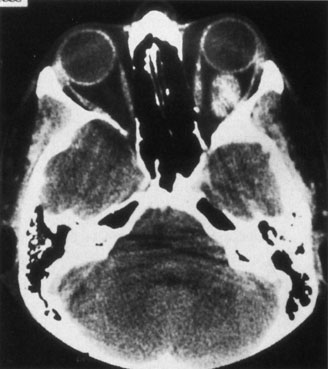

If the clinical suspicion is very high for an arteriovenous fistula, particularly if intervention is required, bilateral selective arteriography of the internal and external carotid arteries is indicated. This shows retrograde opacification of the cavernous sinus and the involved venous drainage system (Fig. 17). A difference in the ocular pulse amplitude (OPA; i.e., the difference between the maximum and minimum intraocular pressure during the cardiac cycle) between a patient's two eyes of more than 1.6 mm Hg may be useful to identify patients with either direct or indirect arteriovenous fistulas.124 This is performed by instilling a topical anesthetic drop into each eye, instructing the patient to look at the 20/400 “E” on a projected Snellen chart, and placing a pneumotonometer tip on the central cornea for 10 to 15 seconds. The difference in OPA between the two eyes then is calculated from the intraocular pressure curves. Ultrasound, CT, and MRI are neither sensitive nor specific. A-scan orbital ultrasonography and Doppler illustrate venous distention and dynamic flow. Color Doppler ultrasonography shows enlargement and arterialization of the venous flow (blood flow reversal), as well as enlarged extraocular muscles and may be useful in monitoring the clinical course of arteriovenous fistulas.109,125 Reversal of flow in the superior ophthalmic vein is not pathognomonic for arteriovenous fistula: It also has been described in carotid sinus thrombophlebitis, orbital apex tumors, and in normal persons.126 Computed tomography demonstrates enlargement of the superior ophthalmic vein and frequently enlargement of the extraocular muscles proportional to the degree of shunting (Fig. 18). There may be CT evidence of venous thrombosis in the form of a nonenhancing defect in the lumen of the superior ophthalmic vein or cavernous sinus. Magnetic resonance angiography (MRA) also may be used to evaluate these lesions, but false-negative results can occur.109

Fig. 18. Direct arteriovenous fistula. Axial computed tomography scan of this patient showing the enlarged left superior ophthalmic vein (white arrow). The rectus muscles of the left orbit were all diffusely enlarged.